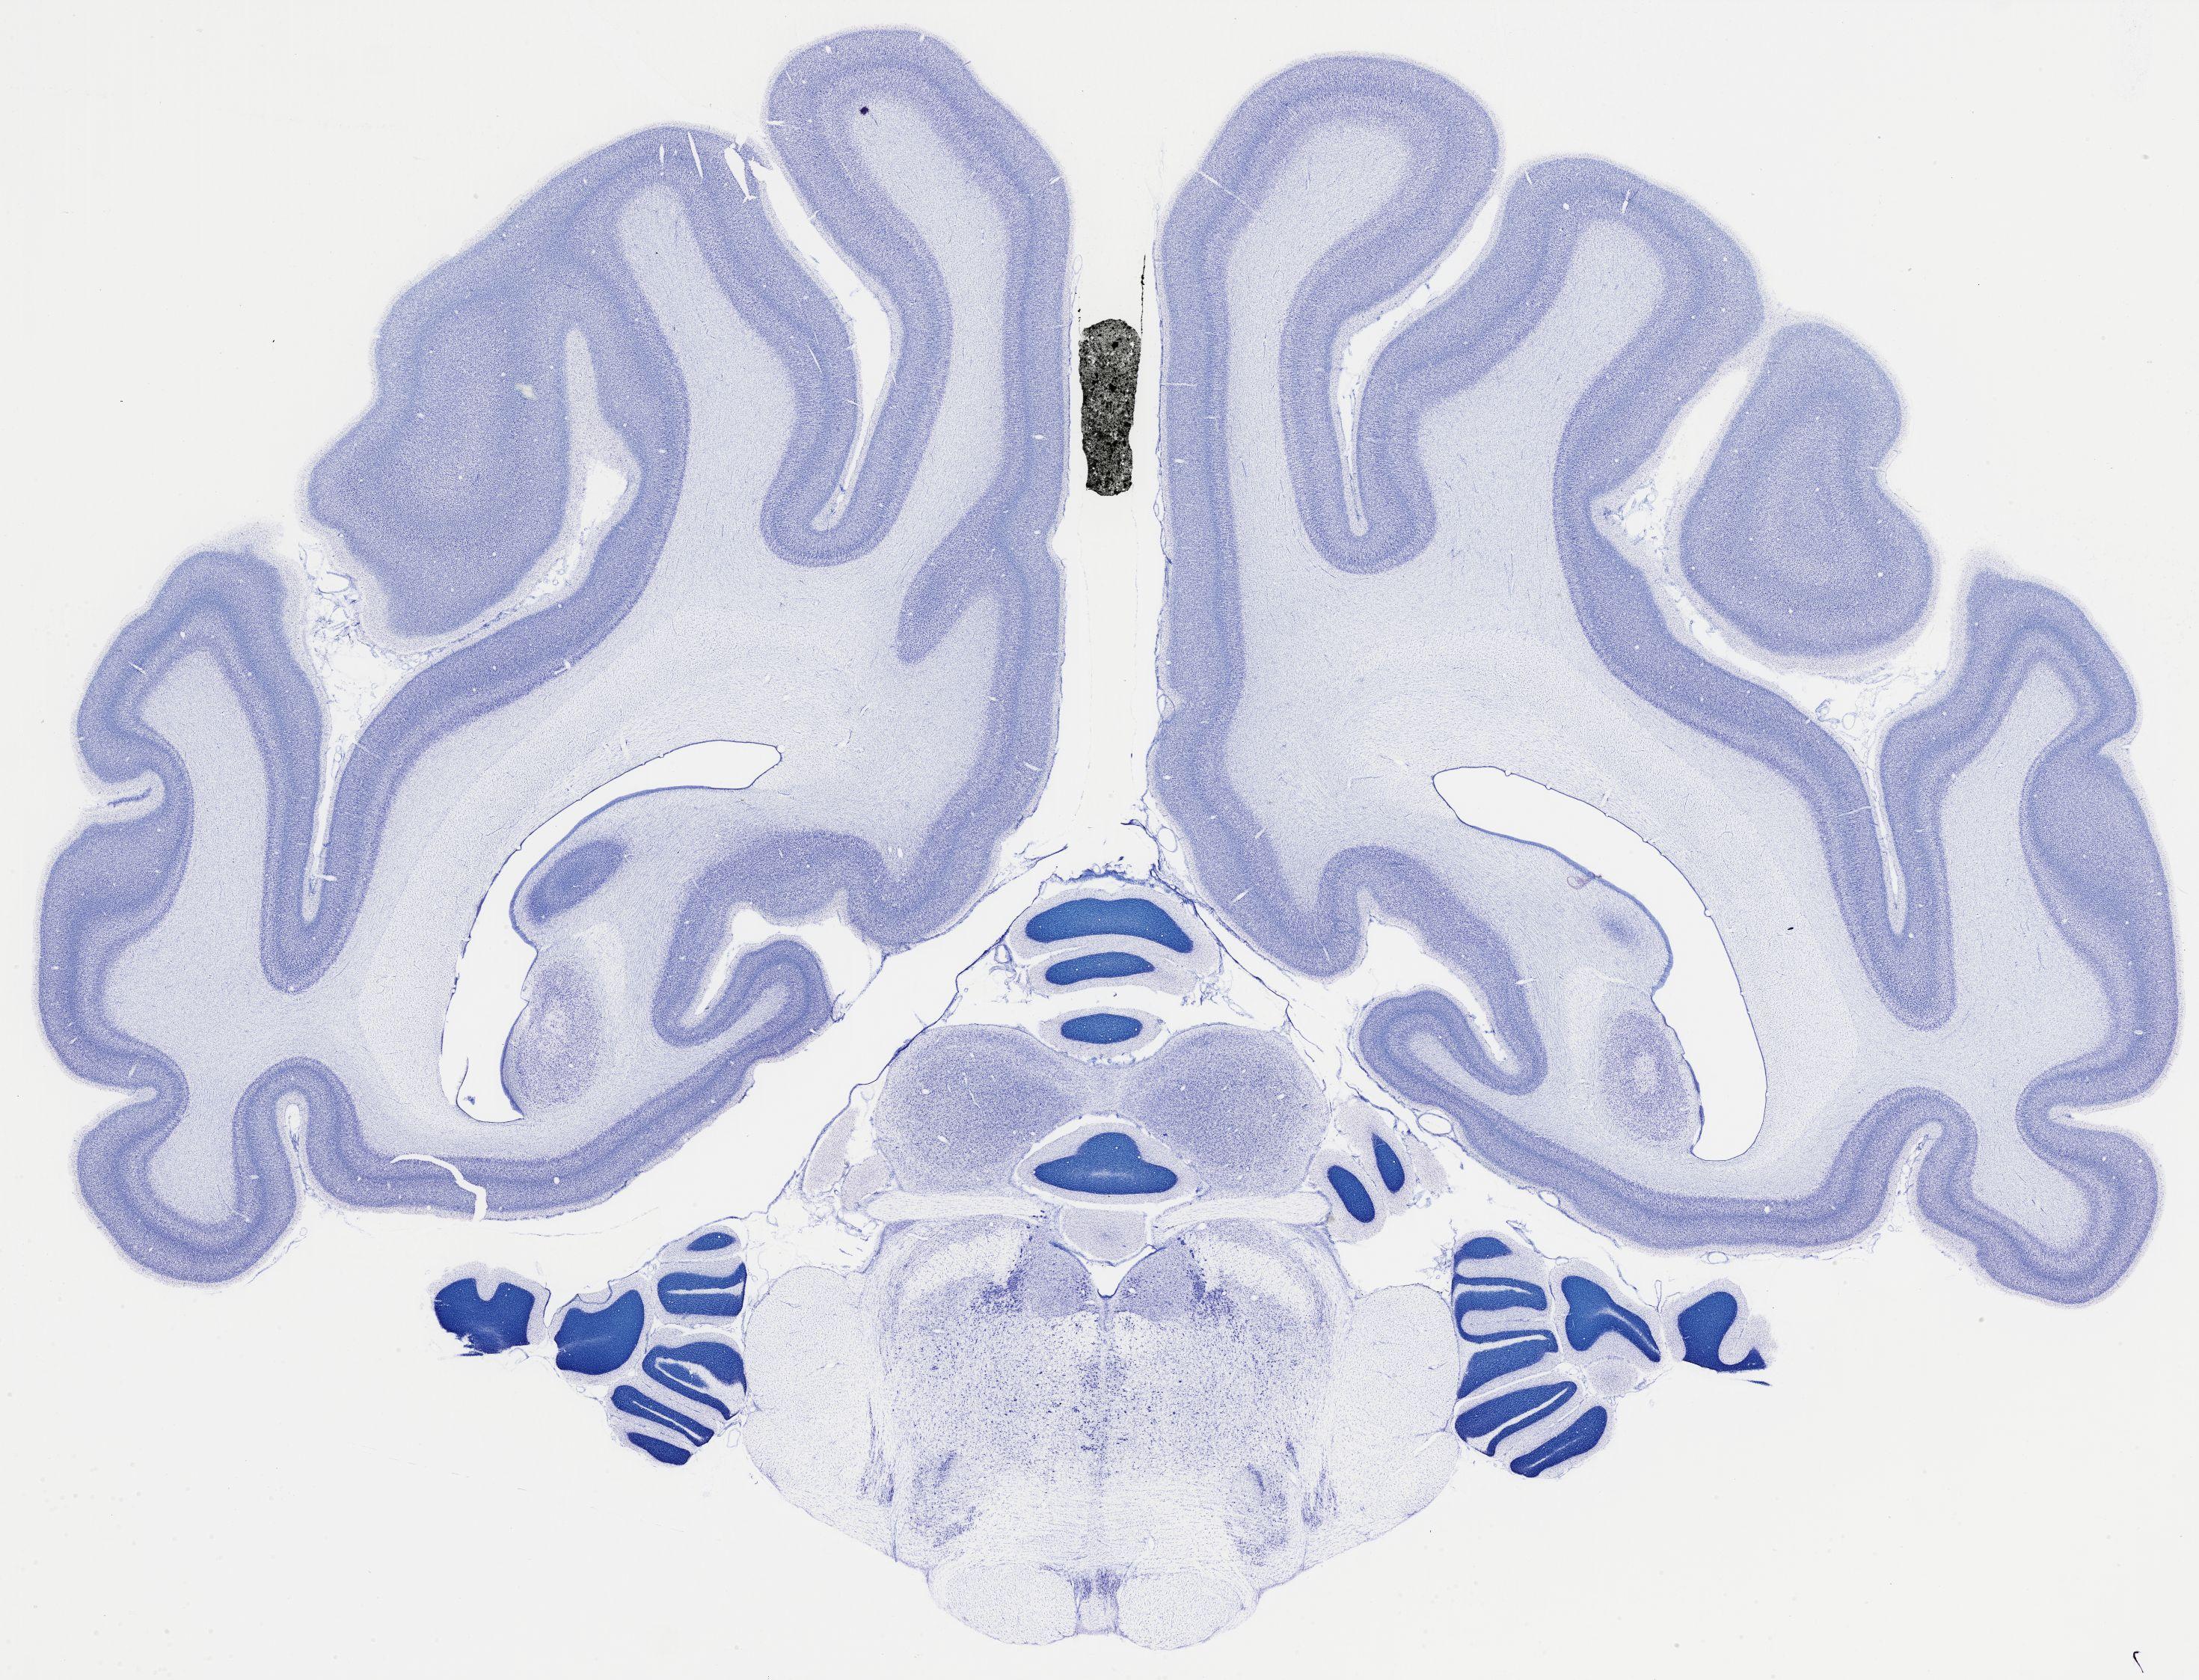

Datasets -> Chlorocebus Aethiops -> Nissl, coronal, histo, Whole-Brain, adult

[ Metadata ]   ·   Source: NeuroScience Associates

thumbnail

522